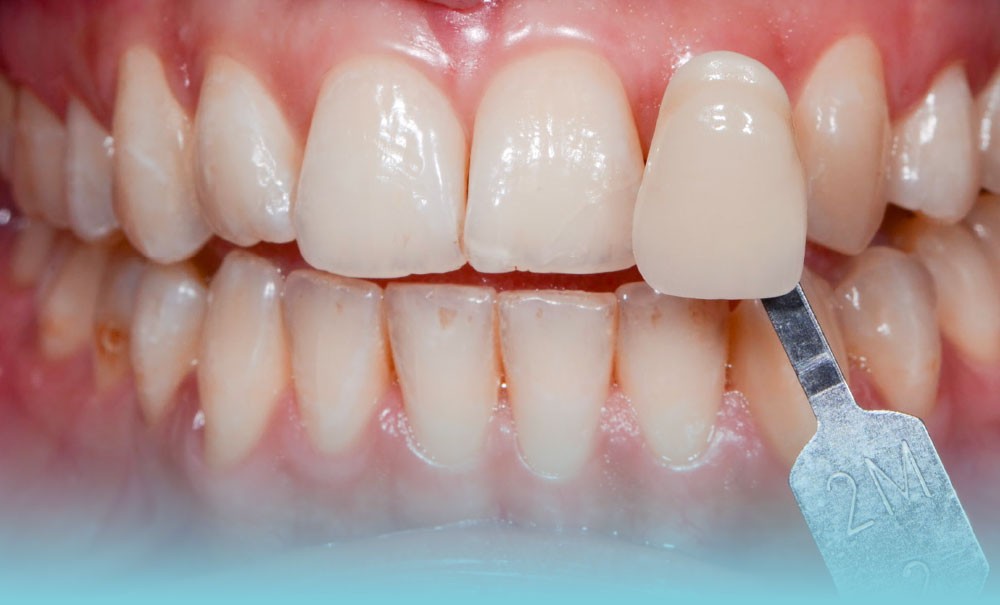

Les dyschromies extrinsèques

Elles sont causées par des agents colorants externes qui se déposent généralement sur la surface amélaire. Leurs origines sont diverses : alimentation (fig. 1b), tabac (fig. 1c), plaque bactérienne ou bactéries chromogènes (fig. 1d), ainsi que certains médicaments. La réalisation d’un aéropolissage en complément du détartrage initial est généralement suffisante pour éliminer efficacement ces colorations. Cependant, le patient doit être prévenu qu’en l’absence de modification de ses habitudes de vie, celles-ci reviendront [2, 4].